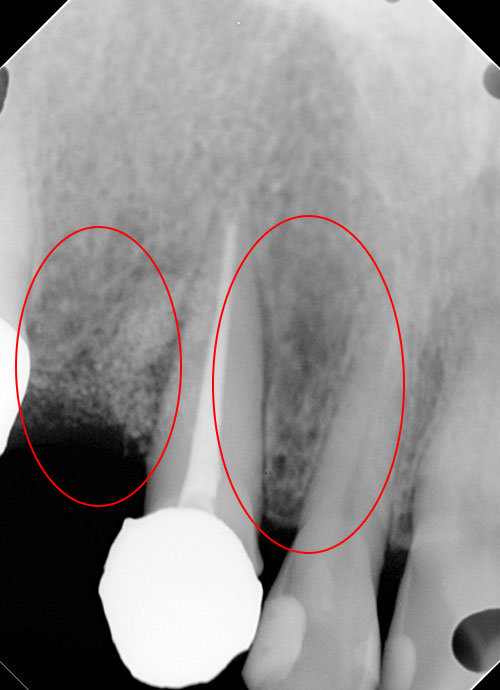

リグロス(歯周組織再生療法)の症例

年齢/性別が表示されたボタンを押すと、下部にスクロールして症例の画像と詳細をご覧になれます。